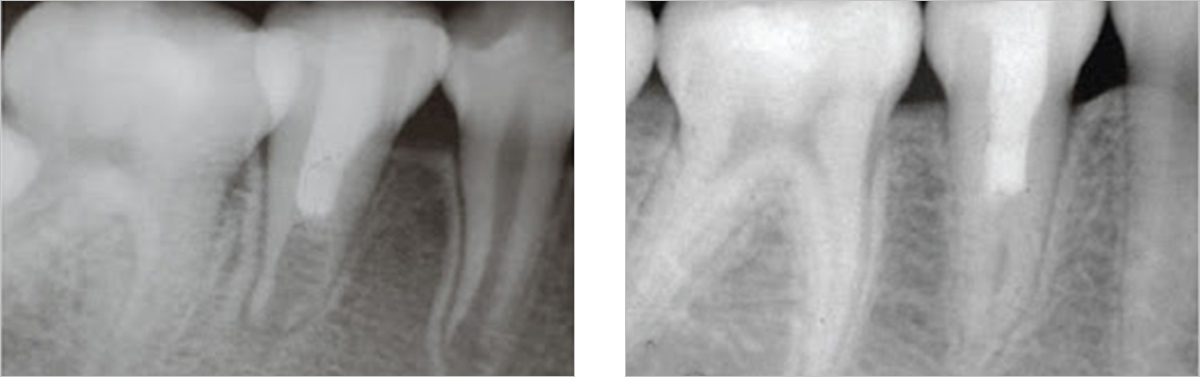

재근관치료

기존의 신경치료 부위에 병소가 재발,치근단 염증이 생긴 경우

비수술적인 재근관치료를 시도해볼 수 있습니다.

치근단 절제술

치근단절제술은 신경치료 후 재신경치료가 불가능하거나

재신경치료를 시행했음에도 치유가 되지 않는 경우에

시행하는 수술입니다.